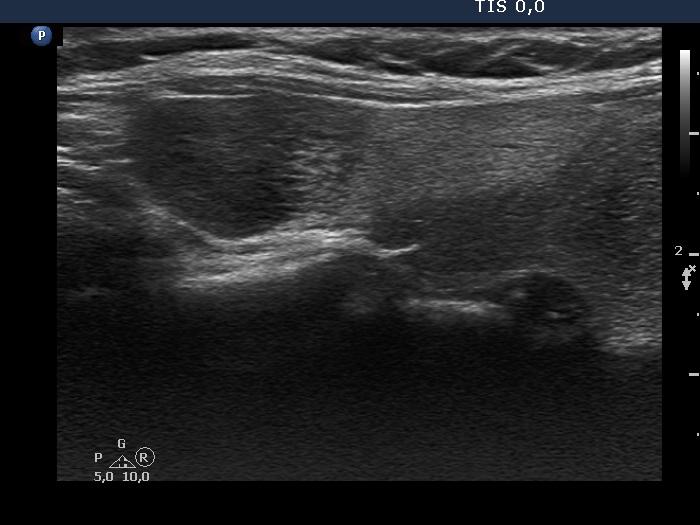

First examination (first, third and fifth rows of images):

Ultrasonography. The thyroid was echonormal and contained multiple inhomogeneous, partly blurred hypoechogenic and moderately hypoechogenic discrete lesions. Multiple lymph nodes were found on both sides of the neck.